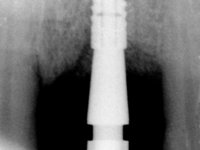

Male patient, 55 years old, smoker. Presented to our dental appointment with a dental implant placed in the area of tooth 21. The gingival architecture in the area lack interdental papilla and showed a vertical deficiency of the soft tissue. Adjacent teeth had significant root exposure.

The angulation of the dental implant did not allow for a screwed prosthesis. Thus, an anatomical abutment was used and the crown margin was milled 1mm infragingival, to allow the removal of the cement. The prosthetic component included a ceramic part emulating the crown and the root of the adjacent teeth, and a gingival part to compensate the soft tissue deficiency. Periodontal surgery to regenerate soft tissue in a vertical deficiency is complex and unpredictable, hence this prosthetic option. Although unconventional, this rehabilitation was well accepted by the patient, easy to perform and proved to be aesthetically satisfying and stable over time.